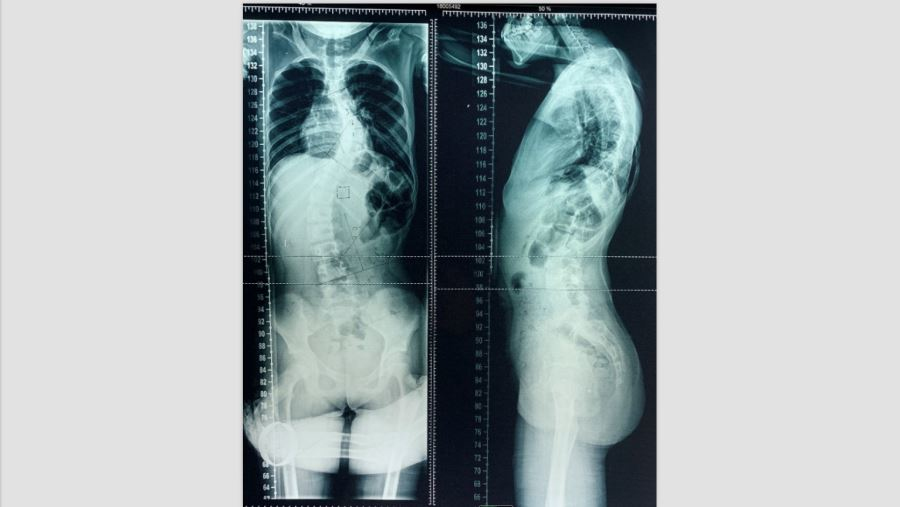

2018年01月患者入院术前X线片:胸部Cobb角71°,腰部Cobb角64°